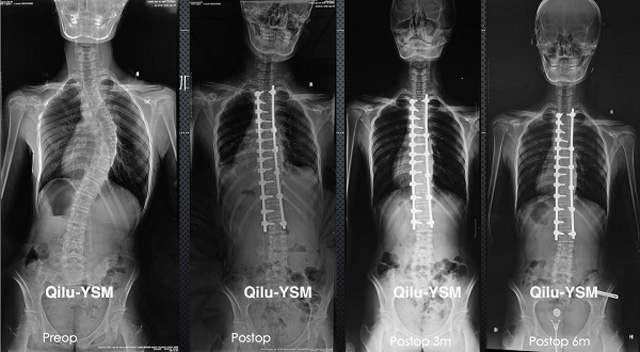

懸吊DR-全電動型機架DR檢查主要用于胸部、四肢、關(guān)節(jié)、脊柱等,主要檢查肺部炎癥、腫瘤、結(jié)核病、四肢骨關(guān)節(jié)的骨折、四肢關(guān)節(jié)、脊柱外傷等。DR就是X光,是一種數(shù)碼影像,曝光時間很短,攝像量很小,影像質(zhì)量也很好,可以說是一種替代CR的方法。DR檢查有其局限性,需要做CT平掃等檢查,周圍淋巴結(jié)的轉(zhuǎn)移以確定病變的良惡性、范圍、大小、與鄰近組織的關(guān)系。